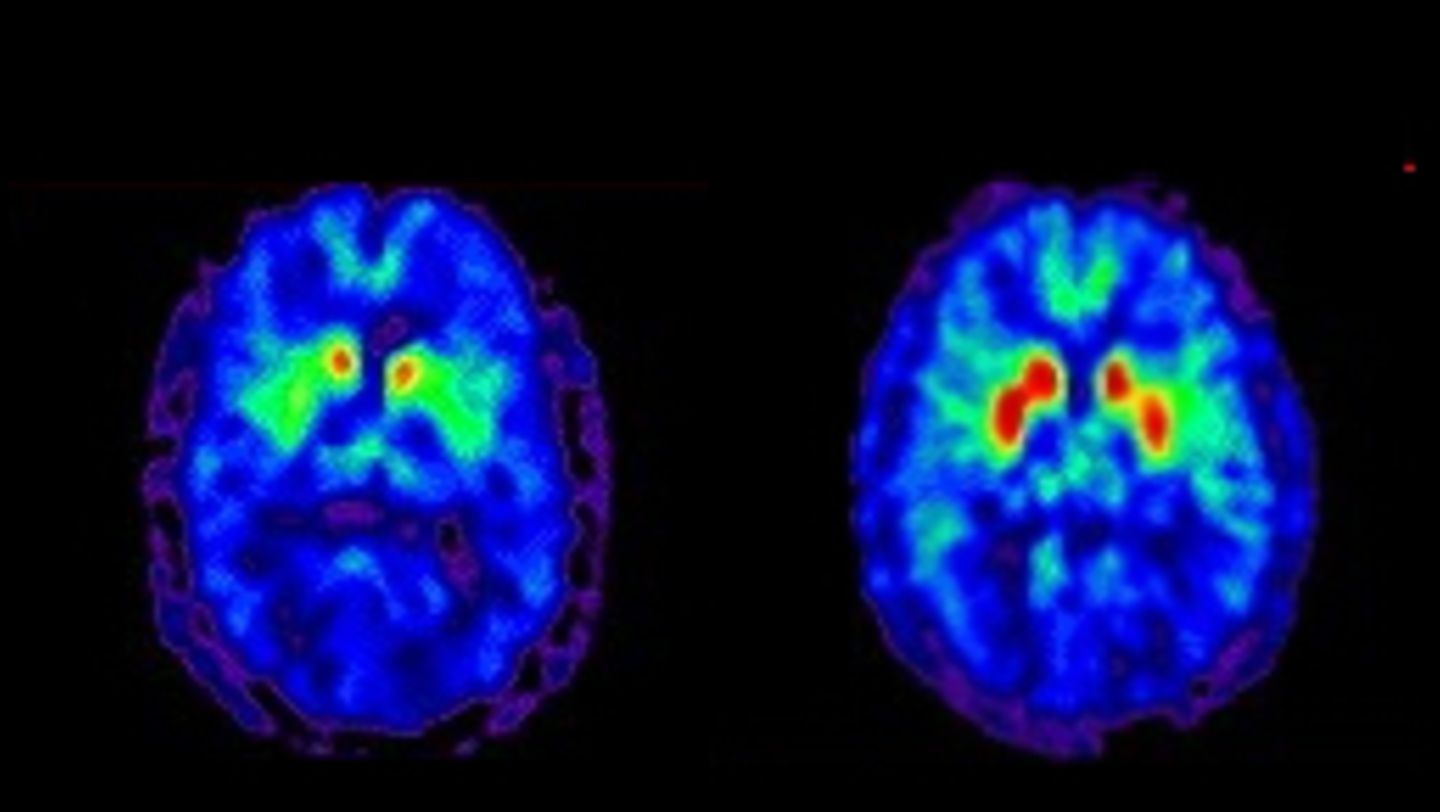

Die typischen Anzeichen einer Parkinson-Erkrankung lassen sich künftig womöglich bis zu 30 Jahre vor dem Auftreten der ersten Symptome nachweisen. Das zeigt eine Studie in der Fachzeitschrift "Neurology". Darin beschreibt das Forscherteam, wie ein Biomarker namens F-AV-133 mittels Positronen-Emissions-Tomographie-Scans (PET) zur Diagnose der Krankheit und zur genauen Verfolgung der Neurodegeneration verwendet werden kann.

Für die Studie erhielten an Parkinson erkrankte Menschen und gesunde Personen innerhalb von zwei Jahren zweimal einen PET-Scan. Bei der Auswertung zeigten sich keine Veränderungen bei den gesunden Personen. Bei den bereits Erkrankten wiesen die PET-Scans jedoch einen erheblichen neuronalen Verlust in drei Schlüsselregionen des Gehirns nach. Mathematische Modellierungen der Forschenden ergaben, dass es bei der Parkinson-Krankheit zu einem über rund 33 Jahre andauernden, schleichenden neuronalen Verlust kommt. Dieser tritt etwa zehneinhalb Jahre früher auf, als sich die Krankheit im PET-Scan nachweisen lässt. Und danach dauert es weitere sechseinhalb Jahre, bis erste motorische Symptome auftreten.